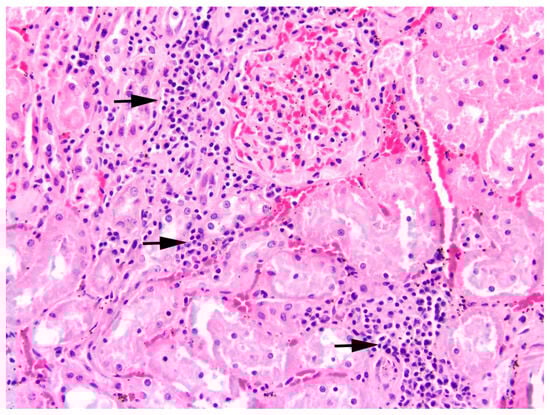

Kidneys: In one-third of the studied animals, inflammation of the kidneys was found (31.0%, n = 48). Whereas no significant effect of hunting ground or sex was observed, age (p = 0.01, Table S1) and sampling year (p = 0.007, Table S1) revealed a significant effect on the presence of nephritis. The prevalence of nephritis was the highest in 2016 (47.2%, n = 25; Figure 11a), with significantly more hares confirmed in post-hoc analyses compared to hares sampled in 2017 (18.8%, n = 9, p = 0.009; Table S2). Between the other sampling years, no significant difference was determined in statistical analyses. Furthermore, significantly more adults were diagnosed with nephritis (37.6%, n = 38) than juveniles (18.5%, n = 10, p = 0.01; Figure 11b).

All inflammations of the kidneys were non-purulent, with interstitial infiltrations of lymphocytes, macrophages, and plasma cells (Figure 12). In one adult male, fibrosis and depression on the kidney surface were observed.